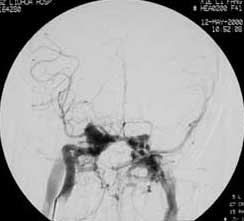

血管内栓塞对于单支或少数供血动脉的AVM,特别是新近出血的病例,可以达到微侵袭、痛苦小、疗效迅速的目的。

近来改变栓塞方式,将导管直接放置 畸形血管团内,注射NBCA胶,可使畸形团的解剖 治愈率提高至27%。再加上更细、超滑的微导管问世,栓塞的并发症更为降低。针对大型、功能区 的AVM栓 塞可缩小其体积,改善血液动力学分布,以利于显微外科技术切除或放射外科治疗,是后二者的重要辅助手段。